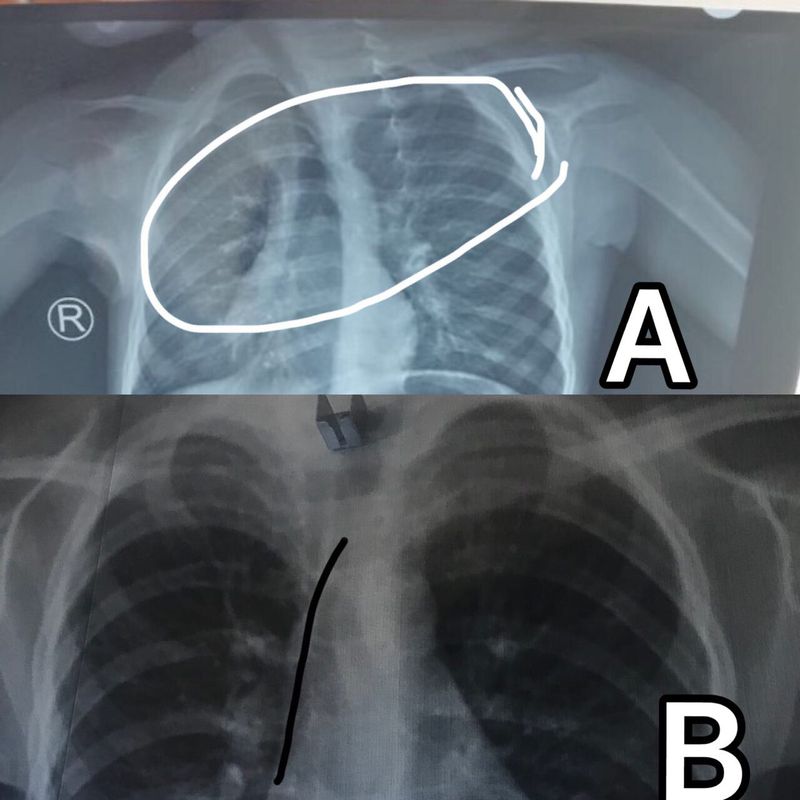

Plain chest x-Ray ,3 y.o male of asthma A) shifted mediastinum with upper left lobe emphysema .B) repeated x_ray next day was normal it’s good point when u suspected unusual abnormality so important to re_investigate